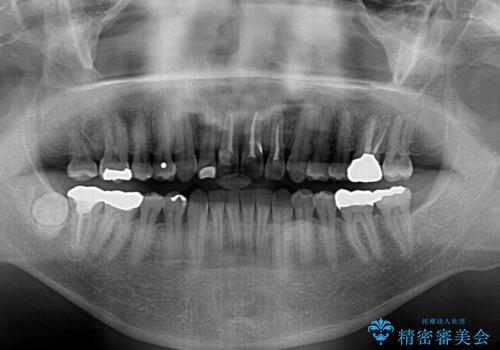

上顎の狭窄歯列 インビザラインによる拡大矯正

20代後半以降の男性は上顎骨の側方拡大処置の成功率が低く、今回も骨を拡大することができませんでした。

しかしながら、歯列を側方に拡大することができ、その後はインビザラインにて叢生を解消することができました。